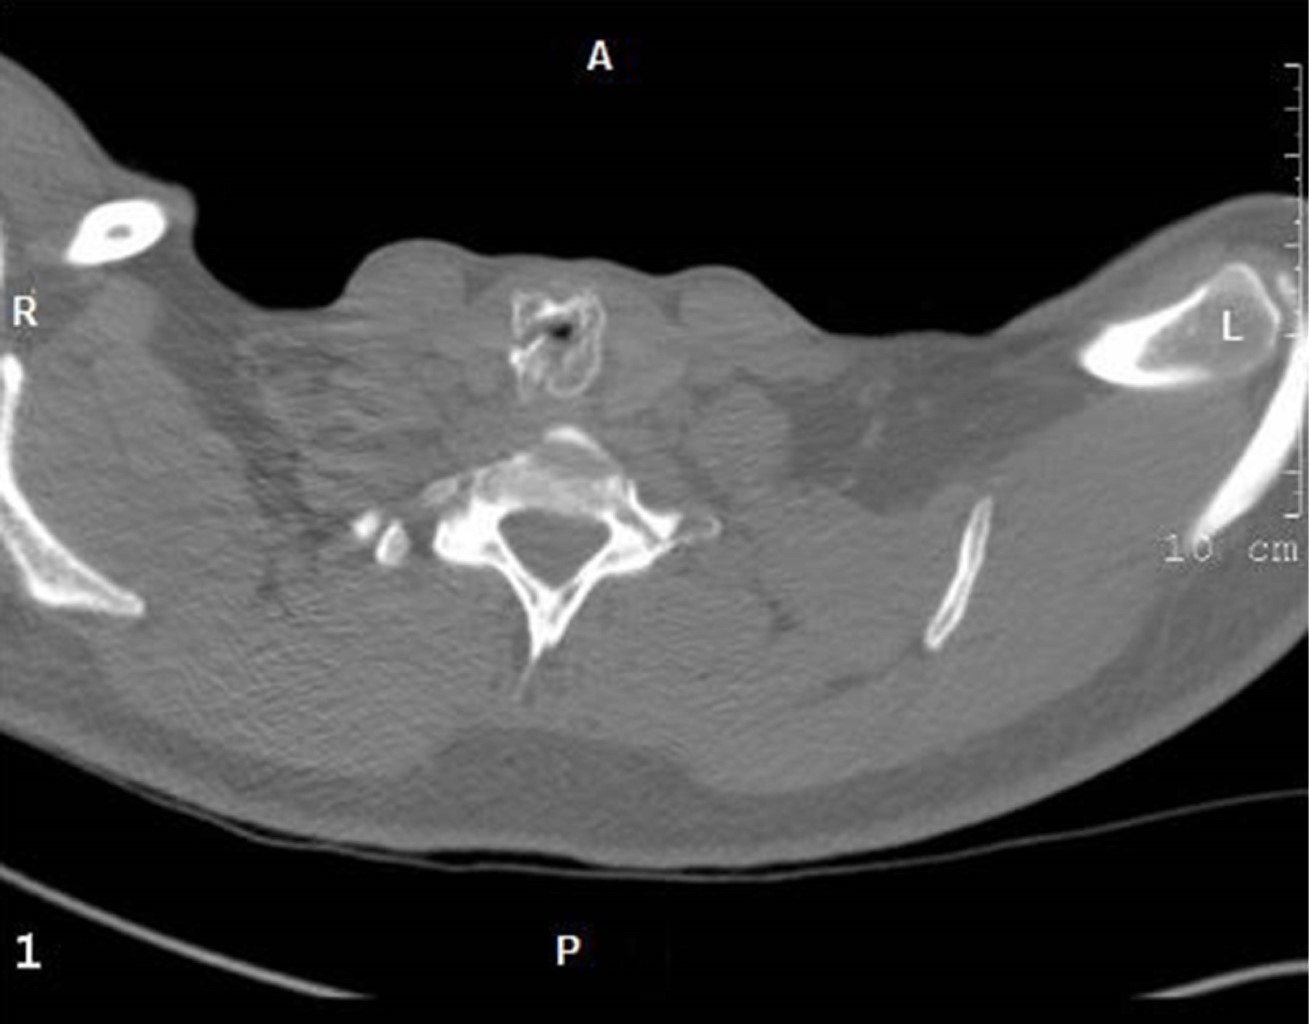

Se realizó un estudio descriptivo sobre una base de datos prospectiva (Access 2010) de afecciones quirúrgicas de la tráquea. Los pacientes, del sexo masculino, con edades de 20, 31 y 35 años, fueron tratados entre 1998 y 2001. La lesión traqueal se produjo mientras viajaban en motocicletas e impactaron contra un alambre (2/3) o una cuerda (1/3) que se encontraban tendidos sobre la vía pública. Todos fueron tratados, inicialmente, en otros centros hospitalarios, donde lograron el control de la VR. Después fueron remitidos para el tratamiento de las secuelas. Los dos pacientes que sufrieron el traumatismo con un alambre presentaron lesiones abiertas, mientras que el que se proyectó contra una cuerda presentó una lesión contusa con fractura del cartílago cricoides (Figura 1). El tratamiento inicial en los centros de origen consistió en traqueostomía y resección traqueal para los tres pacientes y varias sesiones de tratamiento endoscópico (láser) para uno de ellos. Con el fracaso de la resección fueron remitidos a nuestro centro para el tratamiento definitivo. El resultado se consideró satisfactorio cuando el paciente podía reintegrarse a una vida normal, pero tenía una voz débil, y excelente si el paciente pudo reincorporarse a su vida normal, sin limitaciones y la voz era normal.

Al paciente con resección traqueal y tratamiento endoscópico previo se le colocó un tubo en T inicialmente, por inflamación local significativa. En los tres se encontró estenosis subglótica, aunque fueron remitidos con diagnóstico de estenosis traqueal. El enfermo con traumatismo traqueal contuso tenía una fractura del cartílago cricoides (Figura 1).